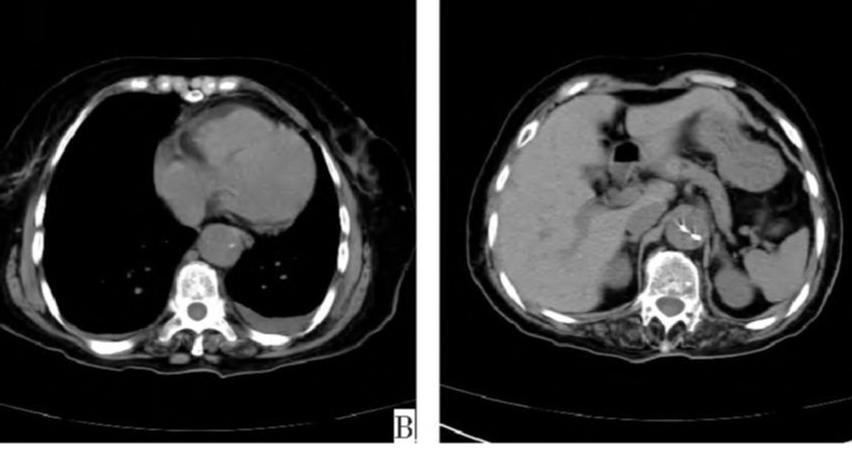

病例8

查到一篇文献,作者虽然用箭头标记了,并且是增强CT,但是鲁迅说:我大约肯定没有看出来,这是主动脉夹层!

图21

病例9

下面这个CT平扫,似乎有大问题!

图22

什么问题?似乎这里有大问题!

图23

同学,你眼神太好使了!

很可惜,这个不是问题,很多CT平扫都有这种线样阴影!

做个增强CT一看,哇,同学,你不光眼神好,运气也不是一般的好!

图24